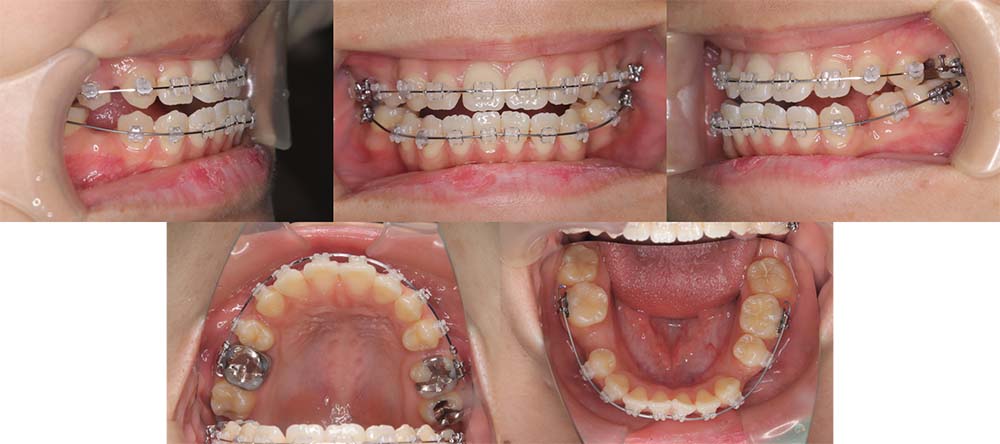

| 症例分類 | 下顎前突、開咬 |

| 診断名 | 上下叢生を伴う開咬 |

| 主訴 | 歯がガタガタ、前歯に隙間があってうまく噛めない |

| 年齢 | 18歳4ヶ月 |

| 性別 | 女性 |

| 抜歯部位 | 右上・左下の第一小臼歯と左上・右下の第二小臼歯 |

| 使用装置 | 表側のワイヤー装置 |

| 治療期間 | 2年9ヶ月 |

| 保定装置 | 固定式保定装置、取り外し式保定装置(8時間) |

| 費用 |

[検査・診断料] ¥49,500 [基本施術料] ¥792,000 [調整料] ¥4,400/回 [抜歯] ¥5,500/本 [保定装置] ¥55,000(税込) 抜歯や虫歯治療は他院にて費用が別途かかります。(抜歯¥4,000〜10,000/本)

他院にて「顎変形症のため手術併用での矯正治療が必要である」との説明を受け、当院を紹介されてご来院されました。骨格的にやや受け口傾向ではありましたが、手術を併用せず改善できる旨をご説明し、矯正単独で治療することにしました

上顎右側第一小臼歯、上顎左側第二小臼歯、下顎右側第二小臼歯、下顎左側第一小臼歯を抜去して治療を行いました。

左下は奥歯を前方に移動させる必要があったため、矯正用アンカースクリューと顎間ゴムを使用して噛み合わせを改善しました。左下の前方移動に時間がかかってしまい、治療期間が予定より伸びてしまいましたが、問題なく咬合させることができました。

下顎の親知らずは将来的に抜去した方が良いことを説明しております。